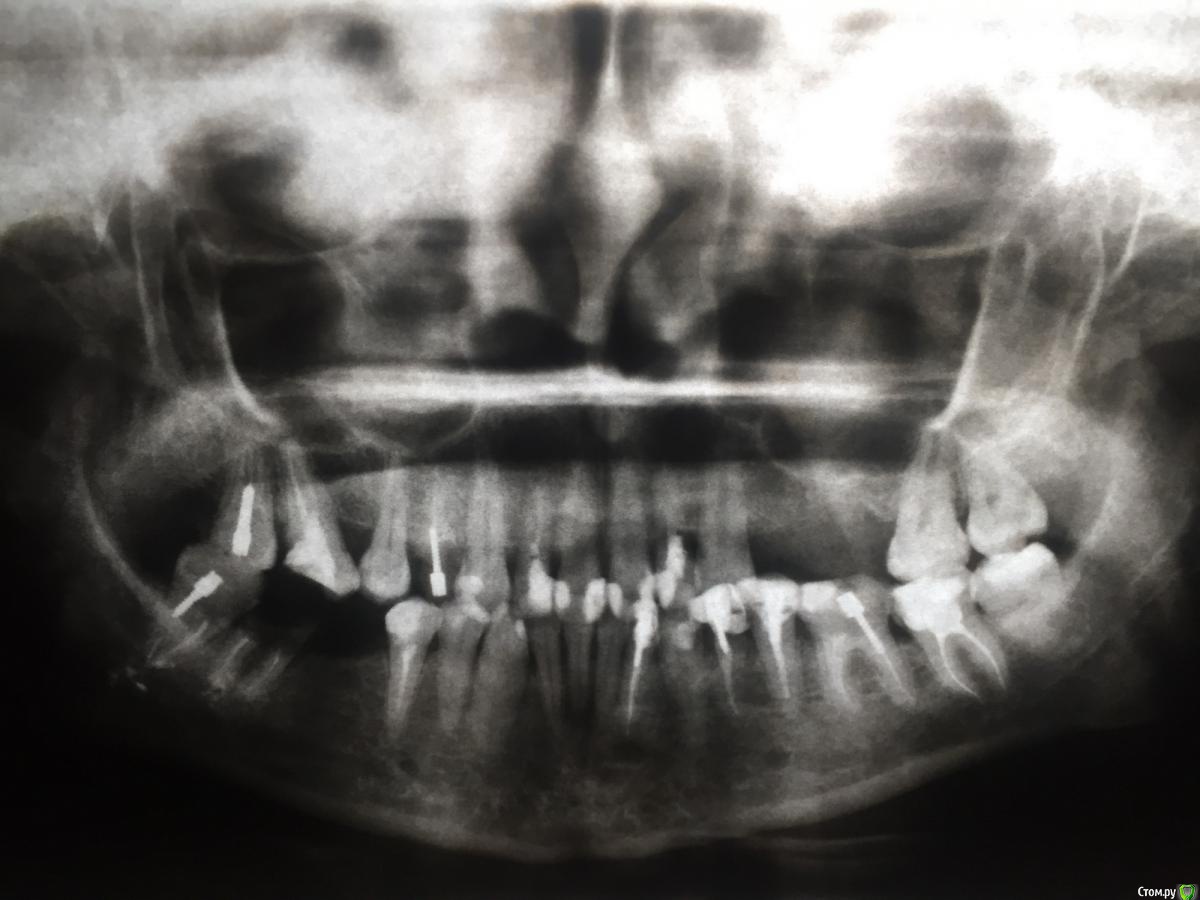

kramer Опубликовано 4 февраля, 2019 Поделиться Опубликовано 4 февраля, 2019 Покажите панорамный снимок 1 Ссылка на комментарий

Ирина 0372 Опубликовано 4 февраля, 2019 Автор Поделиться Опубликовано 4 февраля, 2019 Покажите панорамный снимокОй, вечером загружу, сейчас на работе... 1 Ссылка на комментарий

Ирина 0372 Опубликовано 4 февраля, 2019 Автор Поделиться Опубликовано 4 февраля, 2019 (изменено) ]Покажите панорамный снимокНашла снимок. Но, к сожалению, не свежий.. Это еще до постановки коронок. Могу сказать, что на верхней челюсти изменилось то, что зубы теперь не живые и все каналы хорошо запломбированы. А на нижней слева, внизу, появились три импланта. У меня есть КТ на диске из клиники, где ставила импланты, но почему то файлы не открываются, видимо нужна спец.программа... Изменено 4 февраля, 2019 пользователем Ирина 0372 Ссылка на комментарий

red_butler Опубликовано 4 февраля, 2019 Поделиться Опубликовано 4 февраля, 2019 Нужен актуальный снимок Ссылка на комментарий

Ирина 0372 Опубликовано 4 февраля, 2019 Автор Поделиться Опубликовано 4 февраля, 2019 Нужен актуальный снимокВот ведь..., актуального у меня нет на руках..., он в клинике, где ставила имплантанты. Жаль, извините за беспокойство Не закрывайте пока тему, пожалуйста! Если удастся взять снимок, размещу! Ссылка на комментарий

DmitrySH Опубликовано 4 февраля, 2019 Поделиться Опубликовано 4 февраля, 2019 Если тот снимок не очень свежий, то лучше всего сделать новый. Это не так дорого, но будет намного актуальнее для понимания общей ситуации и состояния зубов после проведенного лечения. 2 Ссылка на комментарий